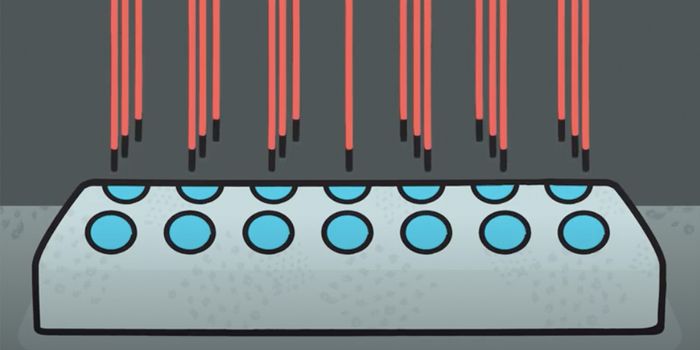

MAY 01, 2018CancerResearchers have developed a microfluidic device that can detect circulating plasma cells in whole blood; therefore, neg ...